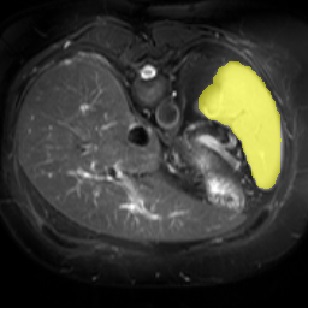

For CMR dataset, we only consider setting 1 because setting 2 is difficult to implement. The results are shown in Table 1 and Figure 4. In general, our proposed method is superior than others. For CHAOS dataset, we consider both setting 1 and setting 2. From the results, we can see the performance of our proposed model is higher than others on CHAOS and CMR datasets. Compared with Q-Net, our mean dice score on CHAOS dataset achieves about 82%. The segmentation results of the model are shown in Figure 5. In setting 2, the slices of the objects containing the test classes are all removed at training stage, and our model still performs well. As can be seen from the Table 2, the segmentation effect of the model on the right kidney is slightly worse than that of ALPNet, but overall, we achieve the best performance. The specific segmentation results are shown in Figure 6. As can be seen from the figure, other methods have excessive segmentation, but ours does not. Our segmentation results are more accurate and reduce redundant segmentation.